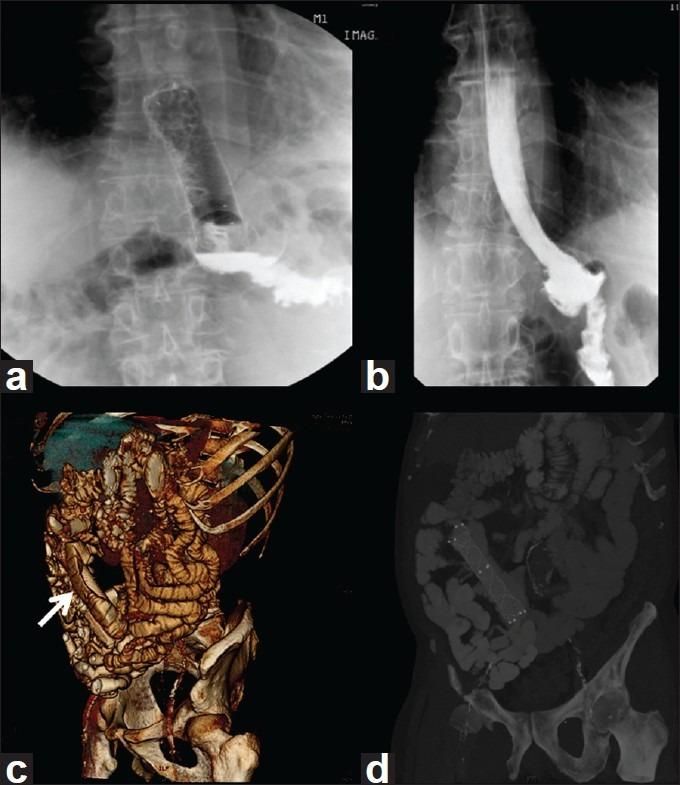

Fully covered self-expanding metal stent (SEMS) placement has been successfully described for the treatment of malignant and benign conditions. The aim of this study is to evaluate our experience of fully covered SEMS placement for post-operative foregut leaks.

Retrospective analysis was done for indications, outcomes and complications of SEMS placed in homogeneous population of 15 patients with post-operative foregut leaks in our tertiary-care centre from December 2008 to December 2010. Stent placement and removal, clinical and radiological evidence of leak healing, migration and other complications were the main outcomes analyzed.

Twenty-three HANAROSTENT(®) SEMS were successfully placed in 14/15 patients (93%) with post-operative foregut leaks for an average duration of 28.73 days (range=1-42 days) per patient and 18.73 days per SEMS. Three (20%) patients needed to be re-stented for persistent leaks ultimately resulting in leak closure. Total 5/15 (33.33%) patients and 7/23 (30.43%) stents showed migration; 5/7 (71.42%) migrated stents could be retrieved endoscopically. There were mucosal ulceration in 2/15 (13.33%) and pain in 1/15 (6.66%) patients.

Stenting with SEMS seems to be a feasible option as a primary care modality for patients with post-operative foregut leaks.